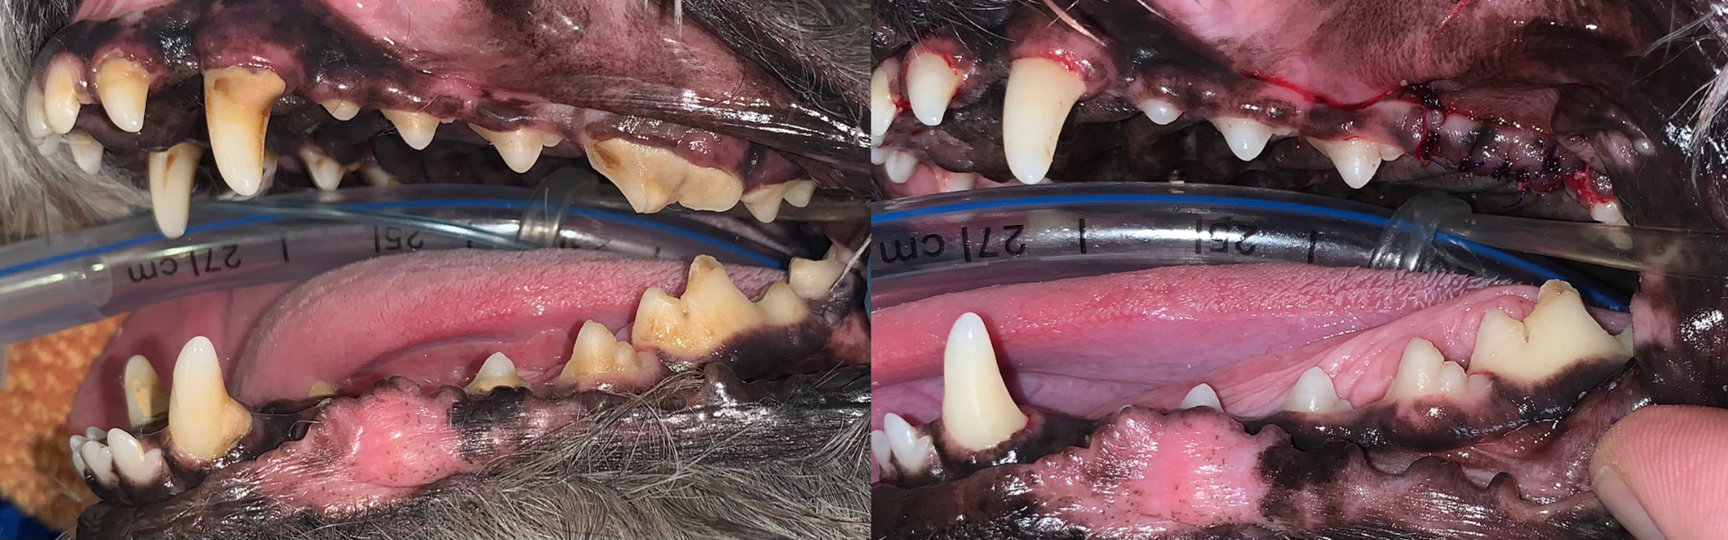

Common dental problems we treat

• Gingivitis and periodontal disease

• Fractured or worn teeth and tooth root abscesses

• Severe tartar and calculus requiring scaling and extractions